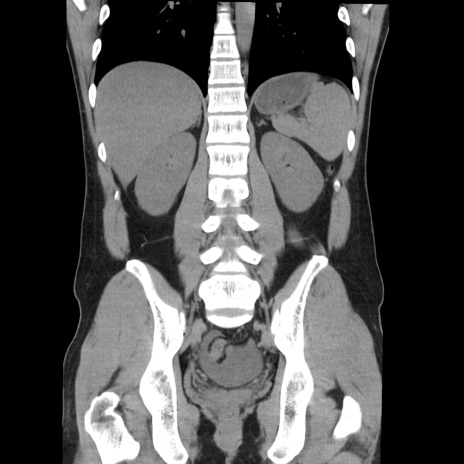

症例36(冠状断像)

【症例】20歳代 男性

【主訴】心窩部痛

【現病歴】今朝より上腹部痛あり。一旦軽快していたが再度出現したため救急要請。昨日夕に白身の魚を含む刺身を食べた。

【身体所見】BP 136/89mmHg、HR 74/min、BT 37.0℃、腹部:膨満、軟、心窩部に圧痛あり。反跳痛なし、筋性防御なし、腸雑音やや亢進あり。

【データ】WBC 17700、CRP 0.48